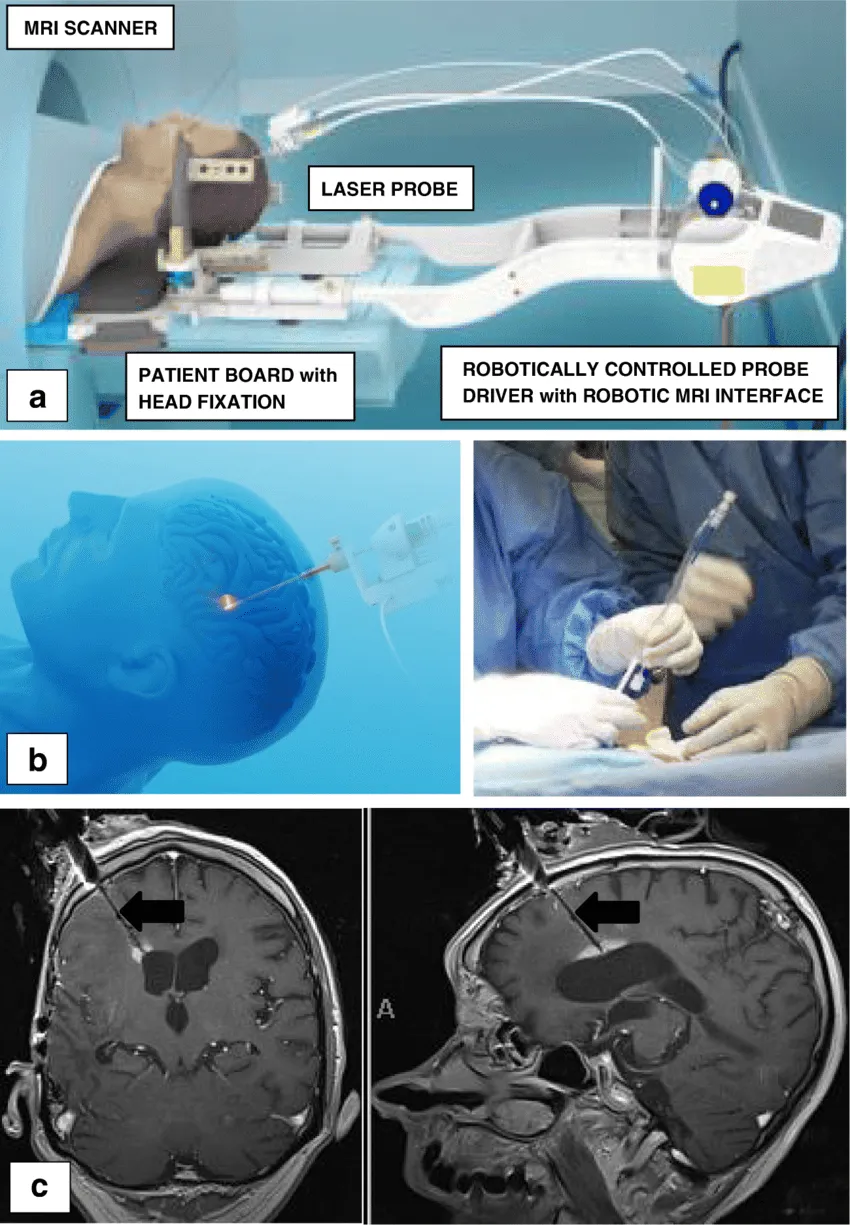

那么有没有无需开颅的手术技术可以轻松“摘除”脑瘤呢?近几年一种磁共振MRI引导的激光间质热疗(LITT)问世,且应用愈加广泛,其使用立体定向技术,可以将纤细的激光光纤直接植入颅内病灶的核心,并使用激光热能破坏病灶,达到类似于手术切除的效果。

总而言之,LITT是具有广泛应用前景的微创治疗颅内病变的新方法。目前,在世界上的超过100家知名的神经外科专业研究机构,LITT技术都正在得到越来越成熟的应用,比如James T.Rutka教授所在的世界水平儿童医院之一加拿大多伦多大学儿童医院SickKids,该医院是较早一批拥有完整LITT疗法设备的儿童医院,其所采用的是Monteris Neuroblate®系统,Rutka教授和他的团队成员已能熟练运用这一微创技术治疗小儿脑瘤和癫痫。

对于LITT技术的运用,Rutka教授还曾总结了这项技术的三个关键要素:立体定向方法,将激光探针精确定位在治疗目标内;手术激光系统随时间变化的热组织消融;MRI热像仪可实时监测温度变化和组织破坏。